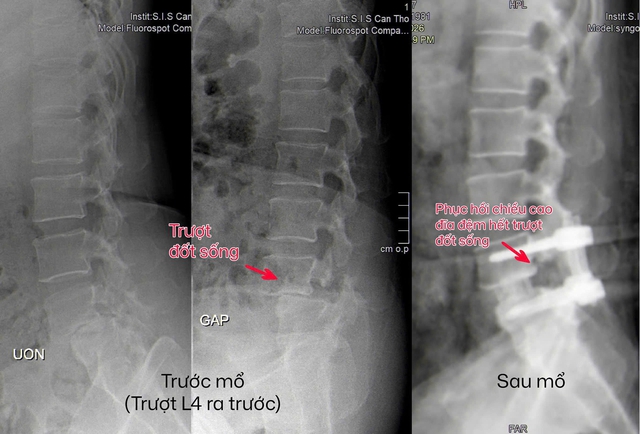

Hình ảnh vị trí trật đốt sống của bệnh nhân, trước và sau phẫu thuật.

Dù đã đi khám nhiều nơi, dùng thuốc, tập vật lý trị liệu và áp dụng các biện pháp dân gian, tình trạng vẫn không cải thiện. Khi đến khám tại Bệnh viện Đa khoa Quốc tế S.I.S Cần Thơ, bệnh nhân được chụp MRI 3.0 Tesla và xác định bị trượt đốt sống mất vững – tình trạng các đốt sống lệch khỏi vị trí bình thường và không còn ổn định khi vận động.

Thông qua một đường mổ nhỏ, dưới hướng dẫn của hệ thống nội soi và hình ảnh hiện đại, các bác sĩ đã giải phóng chèn ép thần kinh; loại bỏ phần đĩa đệm tổn thương; ghép xương liên thân đốt để tái tạo độ vững.

Một miếng ghép được đặt vào giữa hai đốt sống, kết hợp với xương tự thân và vật liệu hỗ trợ để thúc đẩy quá trình liền xương. Sau đó, hệ thống vít qua da được sử dụng để cố định cột sống.